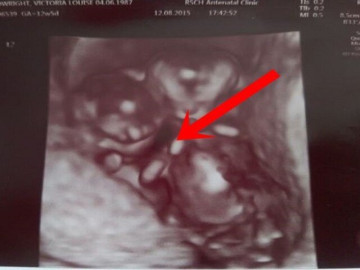

Một người mẫu trẻ sinh năm 9X, sau khi nhiễm virus HPV, đã trải qua thủ thuật khâu vòng eo tử cung trong thai kỳ song sinh của mình.